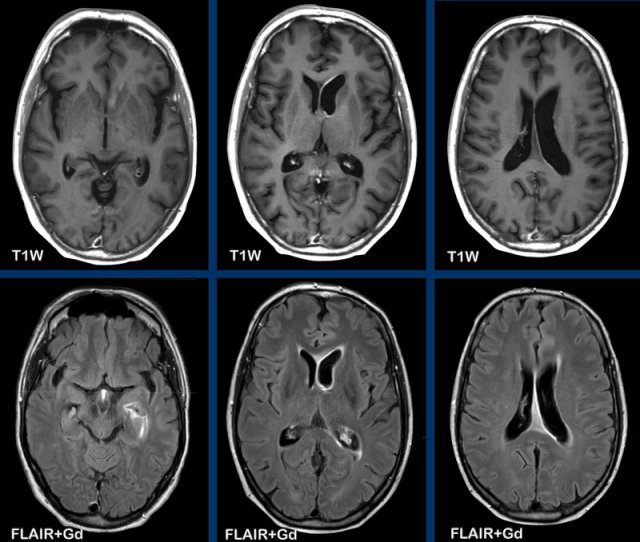

Depiction

of leptomeningeal foci and enhancement can be improved by using contrast-enhanced

FLAIR.

As with meningitis also look at the subarachnoid space at non-contrast FLAIR.

Normally on these images the CSF is suppressed, but in case of pathology the CSF appears more

hyperintense.

A helpful clue for metastasis as differential for meningitis is

the appearance of thick nodular enhancement and the presence of intracerebral

and dural metastases.

Always check the cranial nerves for enhancement.

This is a patient with lungcancer which was complicated by carcinomatous meningitis.

Can you tell which cranial nerves are involved?

Now on these images it is very difficult to see, but if you were able to scroll through the enhanced MRI, you would notice that the following cranial nerves show pathologic enhancement:

- N.III (yellow arrow)

- N.V & n.VI (orange arrows)

- N.VII & n.VIII (blue arrow)

- N.IX t/m XI (white arrow)

Also note the pontine metastasis.

These examples show the advantage of FLAIR+Gd over T1W+Gd in a patient with lung cancer with cerebral metastases and carcinomatous meningitis.

Images

The FLAIR-image better shows the leptomeningeal enhancement around the pons (yellow arrow) and in the cerebellar foliae (black arrowheads).